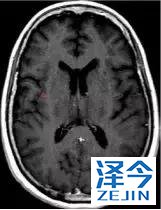

一位77岁的女性患有EPS15-NTRK1 IV期非小细胞肺癌,我们可以看到她的双肺满是病灶,并且出现了肝脏和脑转移,可以说是非常非常晚期了,

肺靶病变达到缓解,我们可以明显的看到前后的图像,病灶明显缩小了,

脑转移病变显示缩小了95%!

初始, 2018年6月 3周期 2018年8月